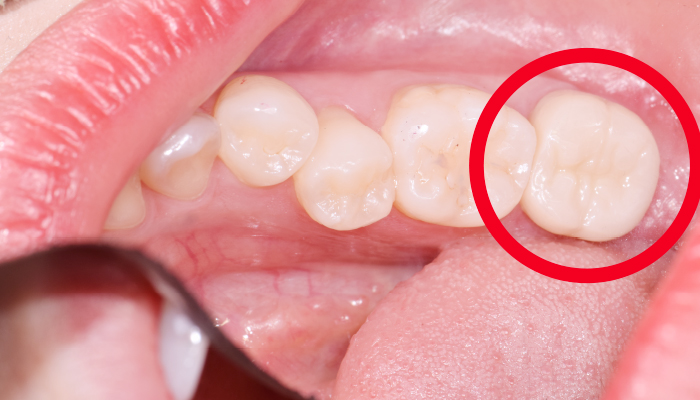

다양한 합병증을 동반하는 이갈이

서울바른훈치과에서는 임상검사 및 바이트스트립, 필요시 치과에서 제작한 이갈이 검사장치를 이용하여 이갈이를 정확하게 진단하고 이와 동반된 치아시림, 턱관절장애, 안면부 근육통, 두통, 사각턱까지 총체적으로 치료가 가능합니다.